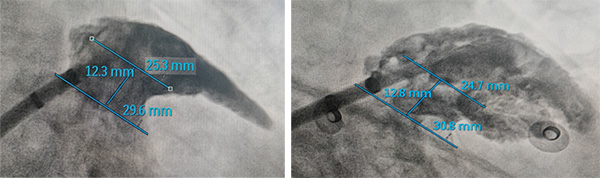

造影:通过造影可见心耳为菜花型,心耳存在两个分叶,且心耳内肌小梁很发达,预定进行嵴外封堵。

测量:通过测量心耳的锚定区为24-25mm,封堵区为29-31mm,综合选择2834LAmbre进行封堵尝试。